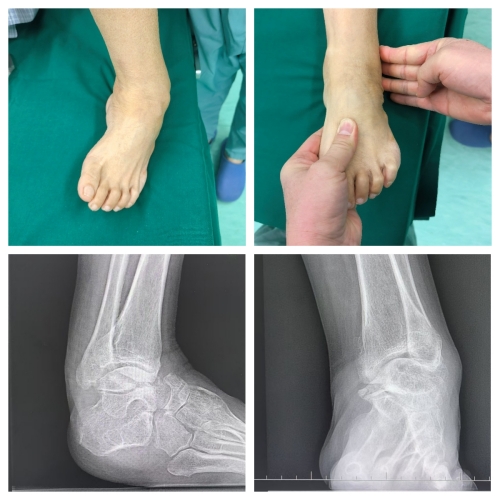

“小时候只是有点内翻,没当回事,没想到越长大越严重。”李女士的声音带着无奈,“后来走路都得拄拐,稍微走几步就疼得钻心,现在只能靠轮椅出门。”随着年龄增长,足部畸形如同藤蔓般生长,一点点侵蚀着她正常行走的权利,将她的生活圈越缩越小。接诊的副主任医师王占国深知,这绝非普通的足部畸形。经过细致查体,真相浮出水面:李女士患的是腓骨肌萎缩症引发的重度马蹄高弓内翻足,距骨扁平、跟骨短宽,踝关节诸骨的解剖关系早已错乱,多处筋膜和韧带挛缩如紧绷的琴弦,关节退变引发的重度关节炎更是让治疗难上加难。

“先天性马蹄内翻足最佳治疗窗口是出生后5—7天,9月龄前干预效果最好。”王占国解释道,“但李女士错过了黄金期,畸形已伴随数十年,软组织和骨骼结构都发生了不可逆的改变,保守治疗收效甚微,只有手术才能为她‘扶正’脚下之路。”这个结论,既坚定了治疗方向,也意味着一场硬仗即将打响。